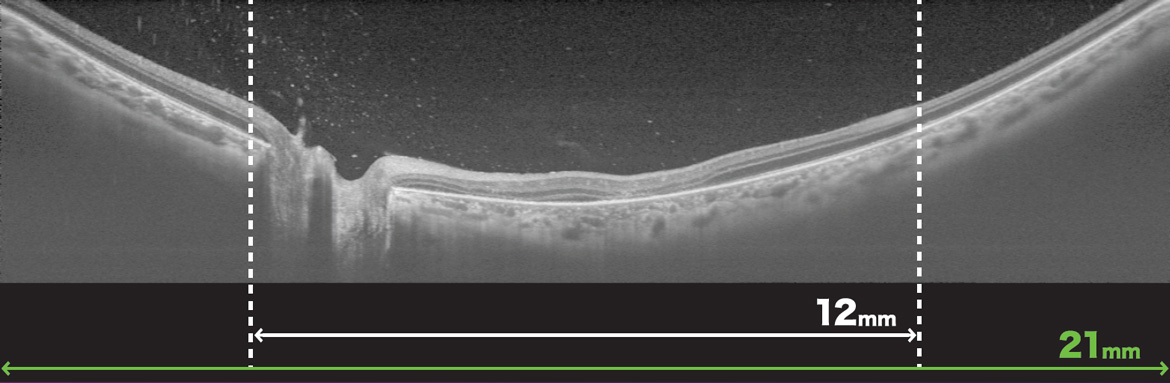

- Wide-Field OCT Max. 21mm Scan

Gather more clinical insights with wide-field OCT and OCTA imaging is valuable in a wide variety of conditions.

The 12x9mm wide-field scan covers the optic nerve and macula and can be captured in one acquisiton to provide a comprehensive assessment of the posterior pole with reference database comparison.